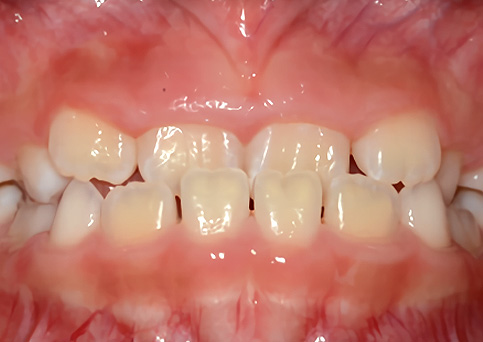

무턱

기능성 교정장치를 통해 작은 아래턱의 자연스러운 성장을 도와주었습니다.

• 주증상

입술돌출, 과개 교합, 무턱

• 치료기간

약 1년

• 부작용

치아표면의 탈회, 치은 부종, 치근흡수 등의 부작용이 있을 수 있습니다.